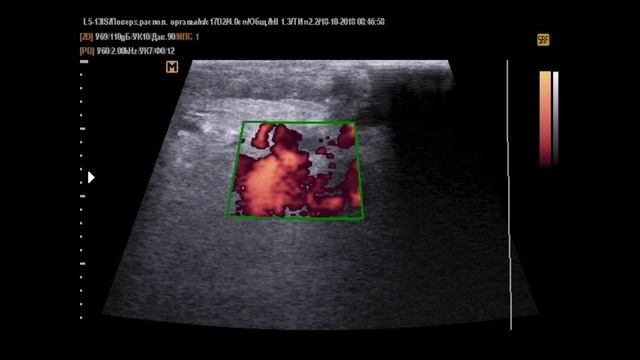

Орхоэпидидимит карта